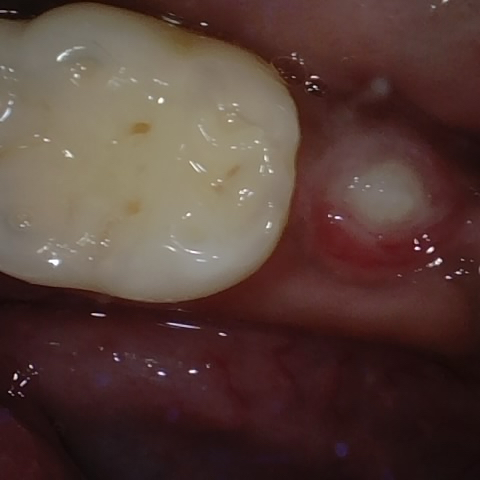

Annotated as "Good"